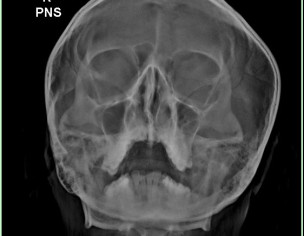

Hr thory din bad Nose block ho jati hai. Someone suggested me for Front sinus X- Ray. Please check kr k bta den kya issue hai

Is there any Nasal Polyps?

polyps are better visualised on ct scan ..xray is showing haziness of sinuses most likely sinusitis..nasal examination required.